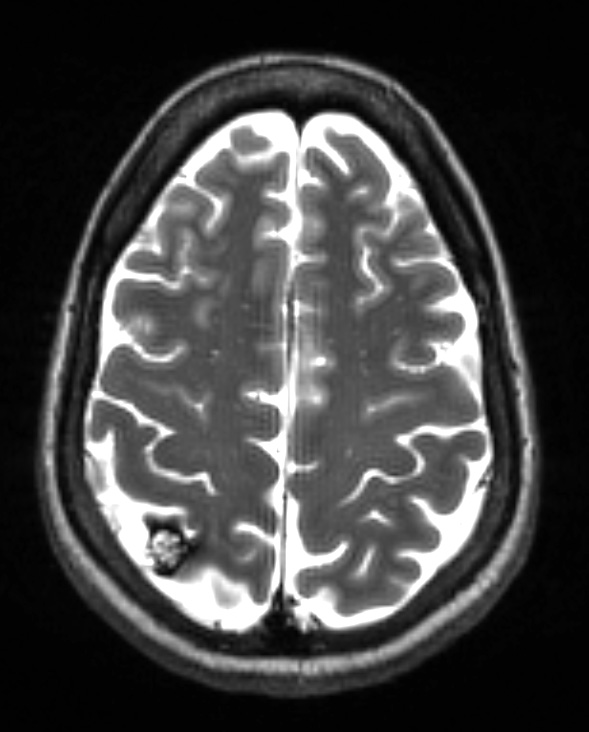

Washington University Experience | VASCULAR | Cavernous Angioma | 10A1 Cavernoma (Case 10) T2 with contrast - Copy

10A1,2 MRI study showed a discrete lesion with a ferruginous penumbra as seen by T2-weighted sequence with (10A1) or without (10A2) contrast.